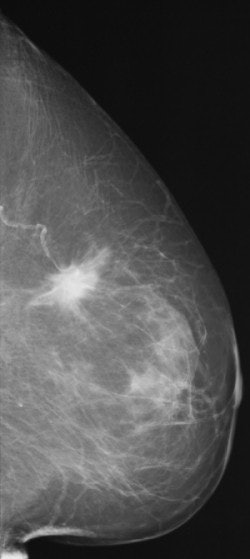

![]() ![]() |

FFDM images acquired on the Senographe 2000D, including zoom (middle) and magnification (below). Images courtesy of Dr. Wolfgang Matzek.